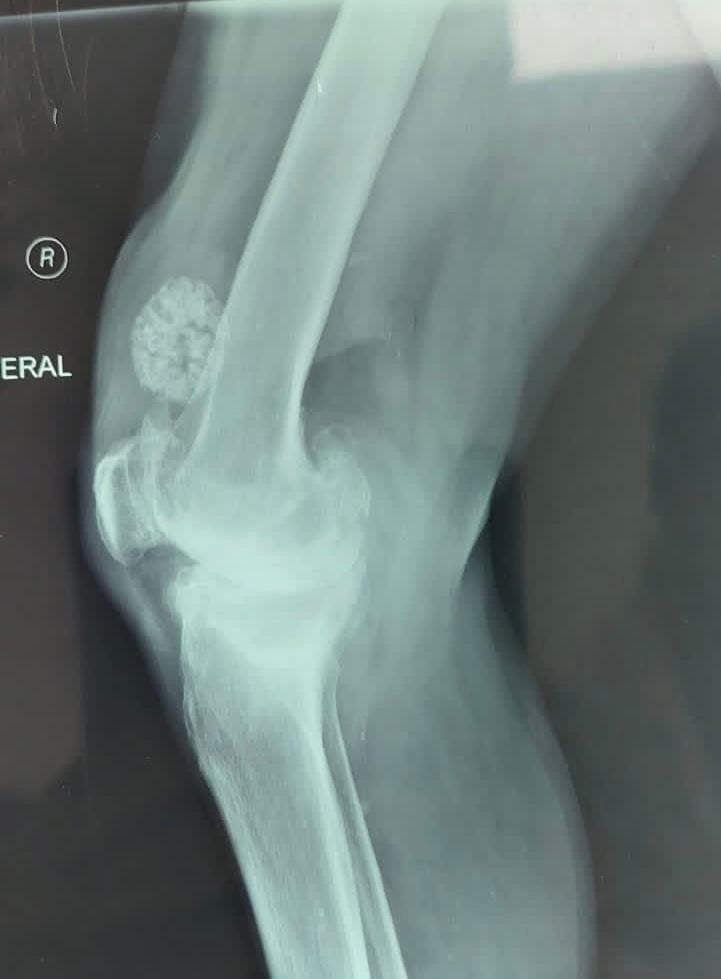

اجرى فرق طبي جراحي عملية جراحية نوعية لرجل يبلغ من العمر ٦٥ سنة يعاني من سوفان شديد وعدم استقرار في الركبه وصعوبة في الحركه وتقوس في الساقين و بعد إجراء الفحوصات الشعاعية اللازمة

اجريت له العملية الجراحية